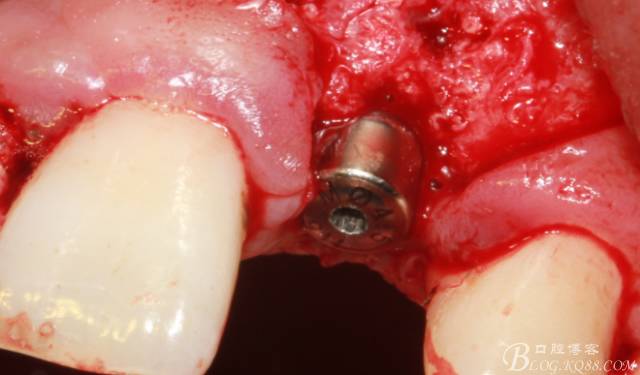

植入植體

縫合